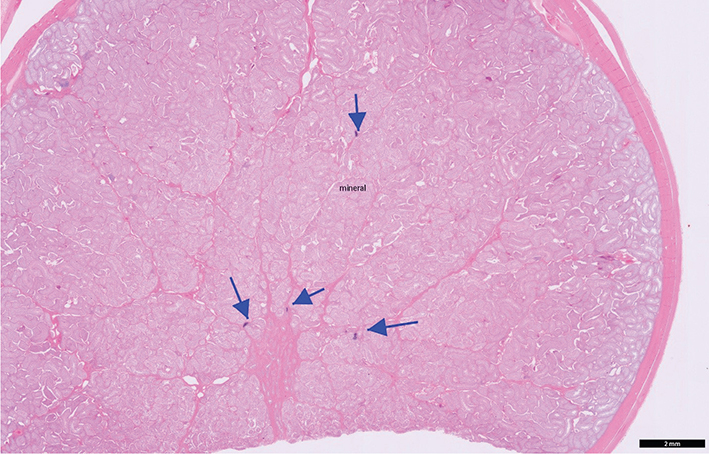

Case 1: A 3½ year, intact male Treeing Walker Coonhound, was presented for ultrasonographic evaluation of the abdomen and testes due to weight loss and polyphagia in July of 2021. Semen had not been evaluated, but the dog had sired a litter in 2020. Left testis appeared normal and had a coarse medium echogenicity throughout; right testis contained hyperechoic foci that were slightly larger than typical testicular microliths observed in human beings but were identical to TM in all other aspects (Figure 1). Other findings on abdominal ultrasonography included a complex cystic structure in the right kidney. Ultrasonography of the testes was repeated in October of 2021 and July of 2022, with no changes noted from the original ultrasonography. In October of 2022, the dog was castrated, due to concern about testicular microlithiasis, a couple of episodes of prostatitis, and retirement from breeding. Right testis was submitted for histopathology; 2 discrete and relatively small foci of intratubular mineralization accompanied by surrounding fibrosis were noted. In these foci, aggregates of fragmented basophilic material, interpreted to represent mineralization, were present within shrunken seminiferous tubules surrounded by a moderate amount of fibrosis (Figures 24) without associated inflammation.

Figure 1.

Figure 1. Testicular ultrasonographic image of Case 1

Figure 2. Testicular histopathology (low magnification) of Case 1